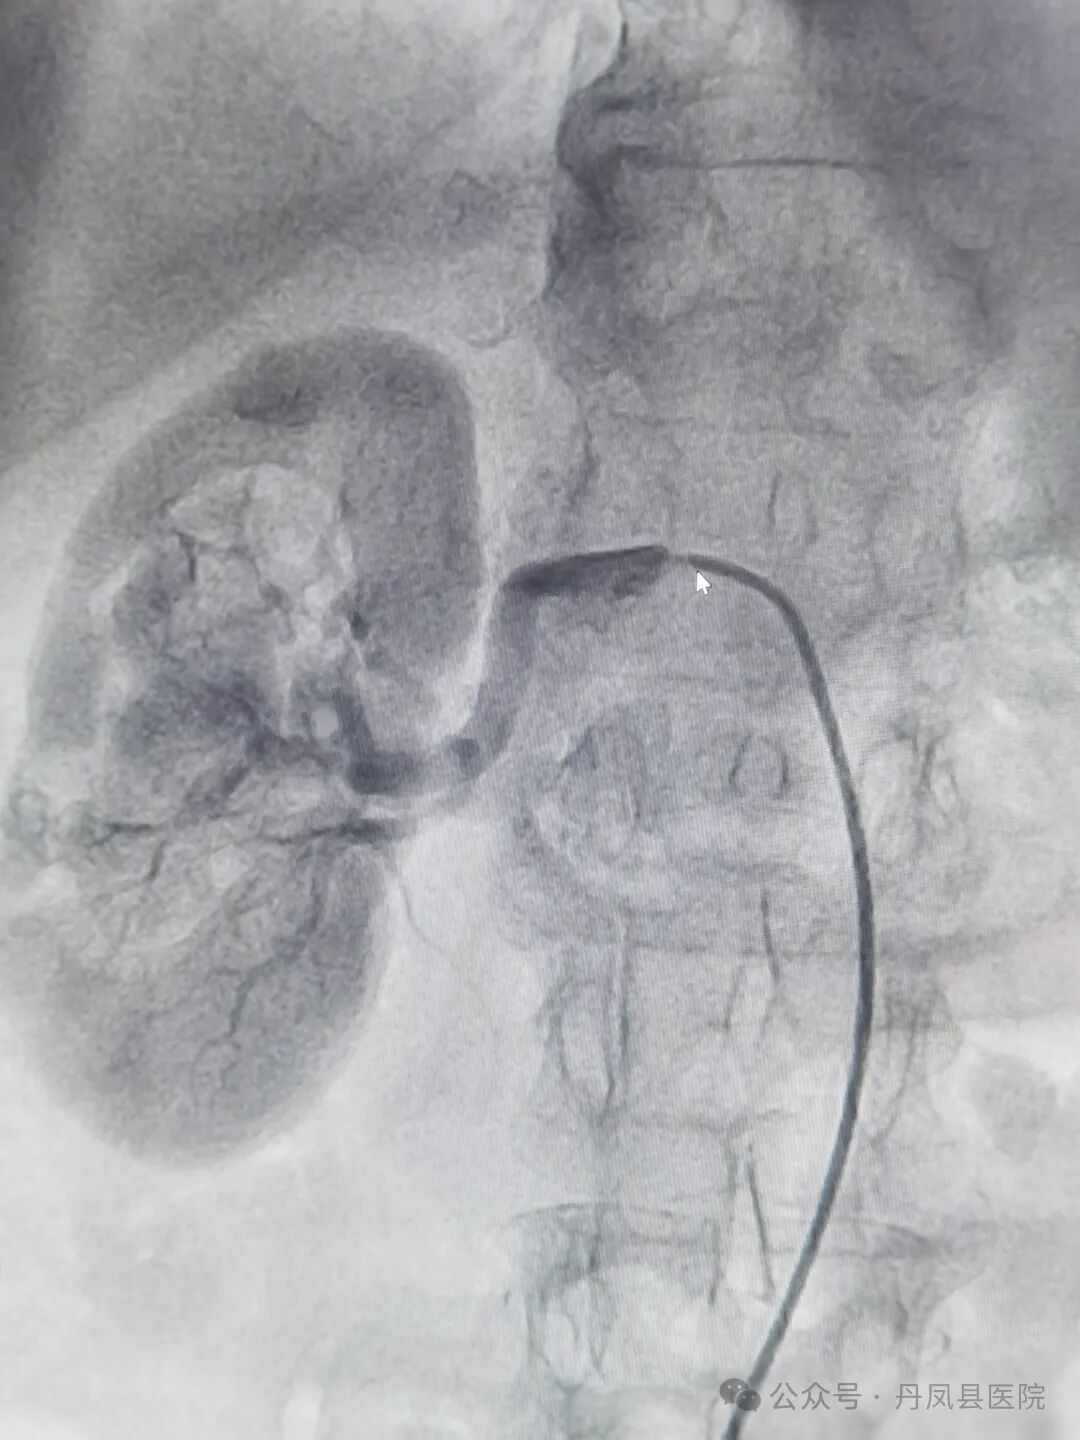

![]()

图为术前右肾动脉起始段90%狭窄![]()